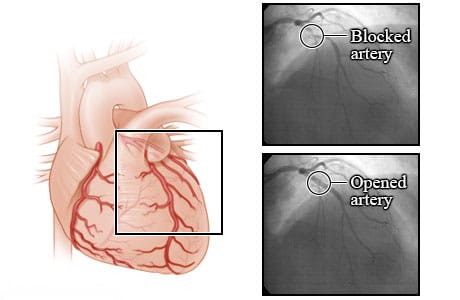

Arteries before and after an angioplasty.

These X-rays show a blocked coronary artery before and after an angioplasty procedure. Before angioplasty, the blood flow is blocked by a narrowed artery. After the angioplasty, blood is flowing better through the newly opened artery. These X-rays are from an angiogram. An angiogram is a test that uses a special dye and camera to take X-ray pictures of the blood flow in an artery.